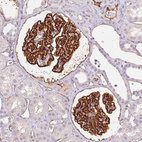

Immunohistochemistry analysis in human kidney and liver tissues using AMAb90643 antibody. Corresponding PODXL RNA-seq data are presented for the same tissues.